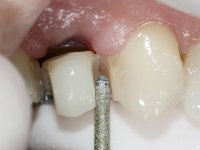

A CT scan was performed to evaluate the available bone heritage and to choose the type and size of implant to be placed. An impression of both jaws was made in alginate, as well as intermaxillary recording for laboratory work on a provisional prosthesis. The provisional prosthesis was made by including a metal wire in a prosthetic tooth adapted to the edentulous space. The root was carefully removed and the implant was placed in the tooth socket corresponding to tooth 1.4. The remaining space between the walls of the alveolus and the implant was filled with regenerative material and then sutured. The prosthesis was previously adapted to the postoperative zone and was then bonded to adjacent teeth. Teflon was used to promote the best possible insulation. Bonding was done using photopolymerizable composite resin using the palatine and inter-proximal walls of the adjacent teeth. After 10 days, the suture was removed and one month later osseointegration was confirmed. Exposure of the implant and placement of the healing screw was performed after 10 weeks. The cervical portion of the provisional tooth had to be reduced to accommodate the healing screw. Stabilized peri-implant soft tissues were impressed using open tray technique with soft and regular consistency putty silicon. In the laboratory the work model was made, along with the choice of pre-fabricated components for the confection of a metal-ceramic crown screwed to the implant with the brand’s interface. Removal of the provisional bridge was done with great care not to touch the interproximal surfaces of the teeth adjacent to the edentulous space. The crown was screwed to the implant, and after imaging, the seating was given the final tightening with 35N of torque. The screw access hole was filled with Teflon and closed with composite resin. The patient manifested satisfaction with the aesthetic and functional rehabilitation achieved.